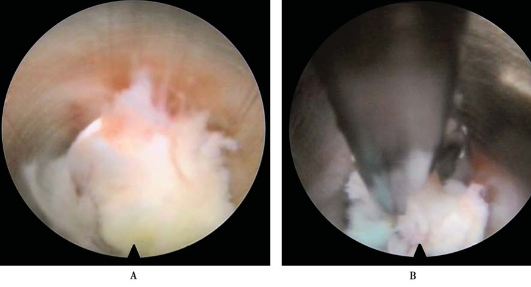

清理工作区:脊柱内镜置入,看到凝血块,小抓钳抓取,射频头止血、消融、探查,分离出工作区(图25)。

图25 清理工作区椎间孔镜置入A.看到血凝块;B.小抓钳抓取;C.射频头止血、消融、探查;D.分离出工作区